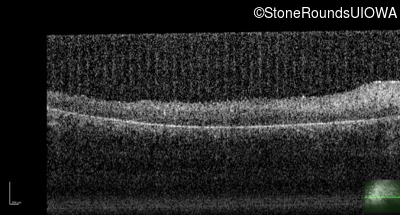

Optical Coherence Tomography - Right - <1/700 sc

Exemplar / OCT Stack